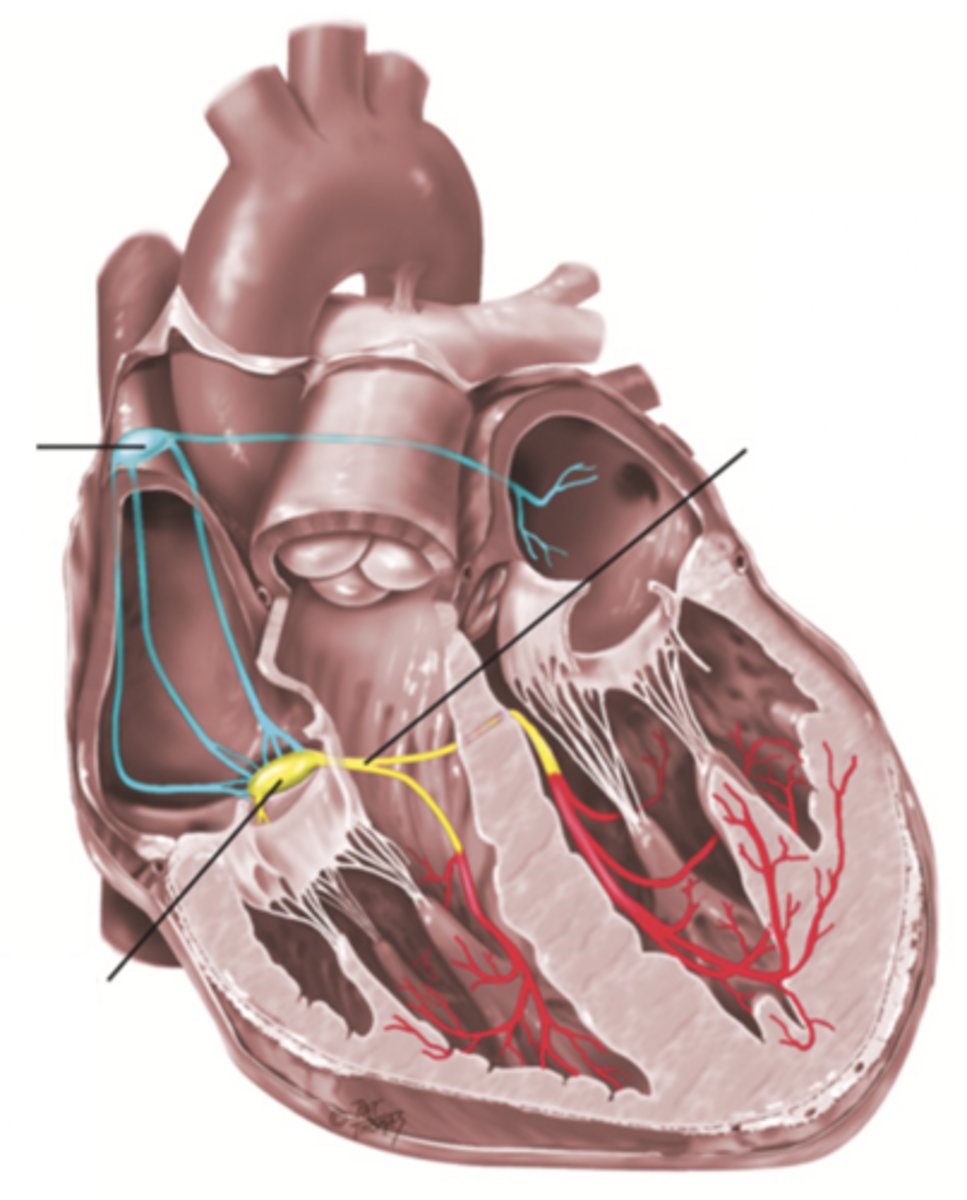

4 Parts of the Heart's Conduction System

- Sinoatrial (SA) node

- Atrioventricular (AV) node

- Bundle of His

- Purkinje fibers

Sinoatrial (SA) Node

Pacemaker of the heart conduction system, located at the right atrium (light blue)

Atrioventricular (AV) Node

The part that relays electrical impulses from atria into the bundle of his in the heart's conduction system; delayed slightly (yellow)

Bundle of His

Part of the heart's conduction system that transmits the cardiac impulse from the atrioventricular node to the purkinje fibers (red)

Purkinje Fibers

Fibers in the ventricles that transmit impulses to the right and left ventricles, causing them to contract